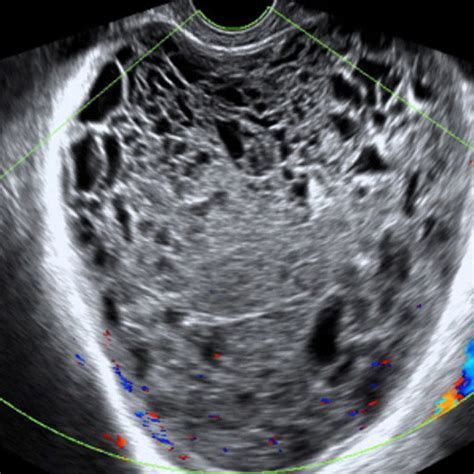

Ovarian Cyst And Cancer Ultrasound Ovarian Cystic Neoplasms

Understand the symptoms, causes, and treatment options for an endo cyst ovary. This guide explains how endometriosis-related ovarian cysts develop, common pain indicators, and effective medical management strategies. Learn how to navigate diagnosis, fertility impacts, and surgical interventions to manage pelvic health and improve your quality of life while effectively addressing this common reproductive condition.